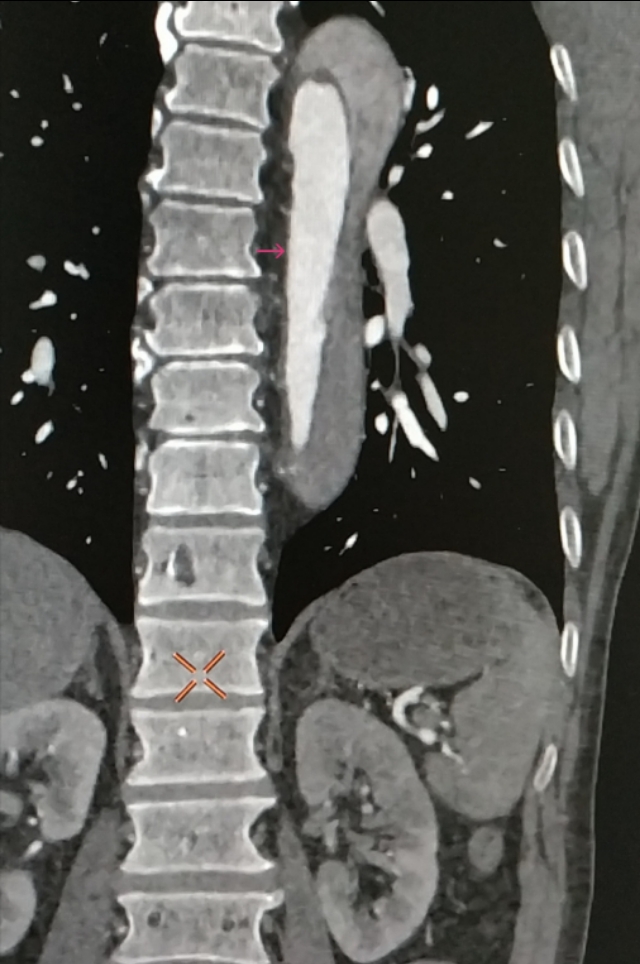

感觉不像,于是带着疑问,跟家属沟通好,我们给患者做了肺动脉和主动脉的全层CTA,发现是那个隐藏已久的杀手——主动脉夹层。而且,是全层撕裂,如下图。

咱们再聊聊主动脉夹层这个病。主动脉夹层是血管撕裂性疾病,指的是人体最大的血管主动脉内膜破裂,血流在经过破口的时候进入中膜,形成真假两腔,类似于双层水杯,类似于轮胎鼓包,这样的一种疾病。死亡风险极其高,多数病人有突发的胸痛,也可以各种症状出现,临床迷惑性极强。